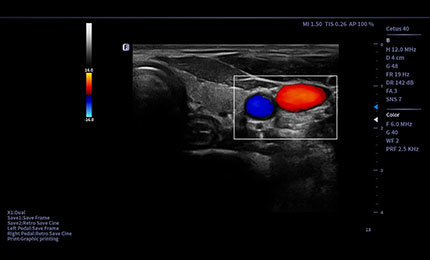

Biopsja

Trzy linie kierujące zapewniające dokładność i bezpieczeństwo. Odległość między dwiema zewnętrznymi liniami może być dostosowana do obszarów zmian, a dostępne są informacje o głębokości igły.